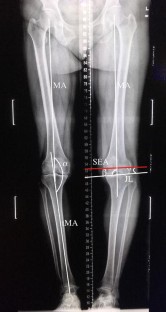

One-hundred and sixty-two knees from 81 Chinese patients undergoing total knee arthroplasty (TKA) were retrospectively investigated. The angle between the medial side of the femoral mechanical axis and the SEA (MA-SEA), as well as the physiological valgus angle, was measured in the coronal plane using three-dimensional reconstruction. The joint line angle (JLA) and hip-knee-ankle angle (HKAA) were measured in long-leg weight-bearing radiographs. The mean of each parameter was compared between the varus (HKAA < 177.0°) and the non-varus knees (HKAA ≥ 177.0°) using an independent t test. Linear regression was used to assess the correlation between MA-SEA with JLA and HKAA.

A total of 42 non-varus knees (6 valgus and 36 neutral knees) and 98 varus knees were measured, as 22 knees were abandoned due to unrecognizable bony landmarks. The mean MA-SEA and JLA were significantly larger in non-varus knees (both, p < 0.01). The mean physiological valgus angle was 5.9 ± 1.0° for Chinese TKA patients and was significantly larger in varus knees (p < 0.01). There was a strong positive correlation between the MA-SEA and JLA (R 2 = 0.35, p < 0.05).